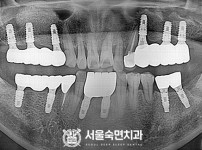

임플란트-전후사진4

치과를-선택할-때-꼭-확인하세요-서울숙면치과-임플란트-전후사진